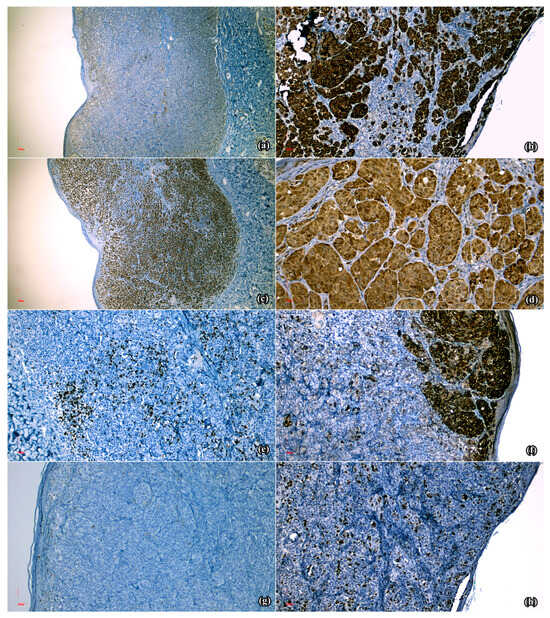

The diagnostic approach involved clinical and dermoscopic assessments that revealed Fitzpatrick phototype II, associated with approximately 30 pigmented nevi exhibiting irregular shapes, diverse coloration (ranging from light to dark brown), and varying diameters. Total body mapping (TBM) was deployed to capture photographic documentation of the entire body surface, followed by sequential digital dermoscopy (FotoFinder bodystudio ATBM master system, 4th Generation, FotoFinder Systems GmbH, Bad Birnbach, Germany) of specific melanocytic lesions, with the goal of analyzing their evolution over time, as well as to identify any newly emerging lesions. Elements suggestive of malignancy (such as irregular borders, shiny white streaks, and irregular pigmented network) were identified in four melanocytic lesions, therefore surgical excision was decided. The histopathological assessment of the pigmented macule located on the cutaneous surface of the left mammary gland revealed atypical melanocytic epithelioid non-ulcerated proliferation, measuring 0.4/0.4/0.2 cm, with massive pattern, a Breslow index of 1 mm, mitotic rate > 1/mm2, and present vascular invasion. Moreover, the lesion developed on the left shoulder had microscopical characteristics of an atypical melanocytic epithelioid non-ulcerated population, measuring 0.7/0.6/0.2 cm, with massive architecture, a Breslow index of 2 mm, significant pagetoid extension and mitotic rate > 1/mm2 (Figure 1c,d). The third excised fragment, originally located in the right lateral cervical region, exhibited an ulcerated proliferation of atypical epithelioid melanocytes of 0.6/0.6/0.15 cm, with massive architecture, a Breslow index of 1.5 mm, present angiotropism and mitotic rate > 1/mm2. The last sample obtained from the left calf displayed an atypical pigmented epithelioid ulcerated proliferation of 0.6/0.6/0.21 cm, with massive architecture, a Breslow index of 2.1 mm, angiotropism and mitotic rate > 1/mm2. Therefore, the final diagnosis was that of ulcerated superficial spreading melanoma, with multiple localizations (pT3b(m)).

S100 (Figure 2a), PAN MELANOMA CK2 (Figure 2b) and SOX-10 (Figure 2c) displayed diffuse positive reactions. P16 had present expression in the cytoplasm and sporadically in the nuclei (Figure 2d), while CD8 revealed positive reaction in the intra- and peritumoral infiltrate (Figure 2e). Moreover, HMB-45 determined positive reaction in the intra-epidermal, superficial dermal areas and focal absent expression in the deep dermal melanocytic population, suggestive of paradoxical maturation (Figure 2f). Finally, Ki-67 generated positive nuclear reactions of variable intensities, ranging from 5% in the tumor on the left shoulder (Figure 2g) to 25% in the right lateral cervical lesion (Figure 2h).

Later, in August 2023, three lesions were supplementarily excised and the microscopical evaluation of the one located on the right thigh (Figure 1a) described an atypical melanocytic epithelioid ulcerated population, measuring 0.5/0.4 cm, with nodular dome-shaped disposition, a Breslow index of 1mm, epidermal consumption without ulceration, mitotic rate of >1/mm2, and intra- and peritumoral brisk inflammatory infiltrate. Moreover, the excised nodule from the left foot displayed, at the microscopic examination, an atypical melanocytic epithelioid ulcerated population of 0.4/0.4 cm, with nodular dome-shaped disposition, a Breslow index of 1.5 mm, epidermal consumption lacking ulceration, a mitotic rate of >1/mm2, and intra- and peritumoral brisk inflammatory infiltrate (Figure 1b). The mass located on the anterior thorax comprised subcutaneous conjunctive and adipose tissue that revealed microscopic characteristics of an atypical melanocytic epithelioid proliferation with nest-like disposition, moderate pigmentation, tumoral necrosis and mild lymphocytic infiltrate, measuring 1/0.8/0.5 cm. Furthermore, supplementary imagistic tests were performed, consisting of thoracic, abdominal and pelvic CT scans, as well as cerebral MRI, in order to detect potential visceral metastases. However, the results showed no pathological masses or changes in the aforementioned explored territories.

Figure 1. Microscopic aspect of the primary melanomas: (a) Atypical epithelioid melanocytic population with nodular, en-dome disposition, Breslow index 1 mm, with epidermal consumption without ulceration and mitotic activity > 1/mm2 (lesion from the right thigh, HE × 10); (b) Atypical epithelioid melanocytic population with nodular, en-dome disposition, Breslow index 1.5 mm, with epidermal consumption without ulceration and mitotic activity > 1/mm2 (lesion from the left foot, HE × 10); (c) Atypical epithelioid melanocytic population with massive architecture, Breslow index 2 mm, with pagetoid extension, but without epidermal ulceration (lesion from the left shoulder, HE × 5); (d) Atypical epithelioid melanocytic proliferation (lesion from the left shoulder, HE × 20).

Figure 2. Microscopical aspects of the immuno-histochemical reactions obtained in the analyzed specimens: (a) Diffuse positive reaction in the melanocytic population (S100 × 5); (b) Diffuse positive reaction in the melanocytic proliferation (MelanA × 10); (c) Diffuse positive nuclear reaction in the neoplastic population (SOX10 × 5); (d) Present expression in the cytoplasm and sporadically at the nuclear level in the melanocytic population (p16 × 20); (e) Positive reaction in the intra- and perilesional lymphocytic infiltrate (CD8 × 10); (f) Positive reaction in the intra-epidermal and superficial dermal component, and focal absent reaction in the deep dermal proliferation (HMB45 × 10); (g) Positive nuclear reaction in 5% of the melanocytic population (lesion from the left shoulder, Ki-67 × 10); (h) Positive nuclear reaction in 25% of the melanocytic population (lesion from the right lateral cervical region, Ki-67 × 10).